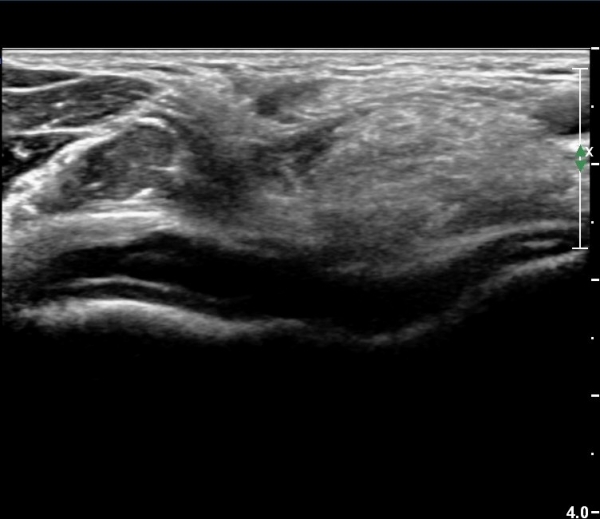

ÃÊÀ½ÆÄ °Ë»ç

ÆÈ²ÞÄ¡ ¾ÕÂÊ ¼ÒµÎ Á¾´Ü¸é°Ë»ç¿Í Ⱦ´Ü